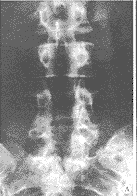

图2 1位33岁患者手术前、后X线照片

Fig 2 X-ray image of pre-operation and post-operation of a 33-years-old patient

A 33-year-old male, complained of lumbar pain and bilateral lower extremity pain caused by post-operative lumbar instability after a previous lumbar lamiectomy (spondylolisthesis of L5~S1) and degeneration of L4~5)。 Two segmental PLIF with single BAK additional with Steffee interfixiation was performed. A: Pre-operative post-anterior image; B: Post-operative anter-posterior; C: Lateral image

本组随访时间平均12.5个月(6~18个月),除1例影像学显示BAK融合器周围存在透明带, 判定为融合失败外,余皆达到临床融合(图1,2)。患者主观自我评定,12例满意,6例基本满意,2例认为可以。